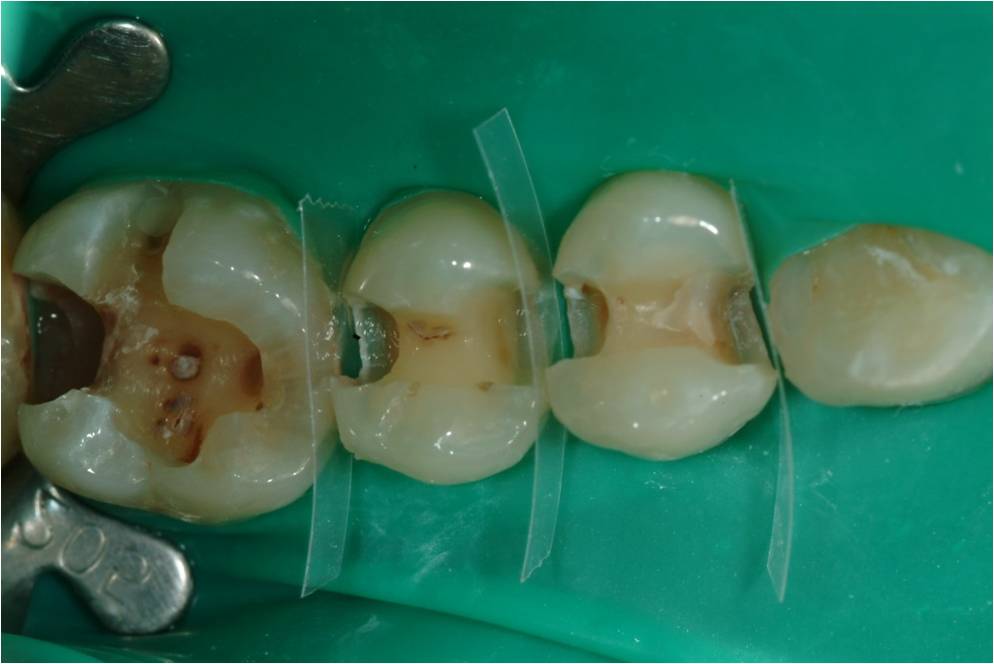

崁體窩洞製備